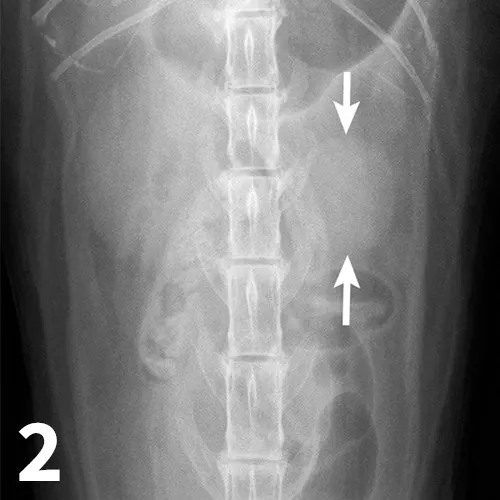

Survey abdominal radiographs (Figures 1 and 2) offer important information on kidney number, size, shape, symmetry, and location, as well as the presence of any mineralized opacities (eg, calcified tissue, nephroliths). The utility of abdominal radiographs is decreased in patients with abdominal fluid or lack of abdominal fat (eg, young or emaciated patients) because of lack of contrast. Excretory urography (IV pyelography), although more invasive, can augment survey radiographs and provide information about renal parenchymal architecture (eg, filling defects associated with cysts or infiltrative disease), the renal pelvis, and ureters as well as a qualitative assessment of global and individual renal excretory function (Figure 3).

An enlarged left kidney with an irregular shape (arrows) is noted on the VD view of a dog with renal adenocarcinoma. The left kidney measured 4.5 times the length of L2; normal kidney length in the dog is 2.5 to 3.5 times the length of L2.